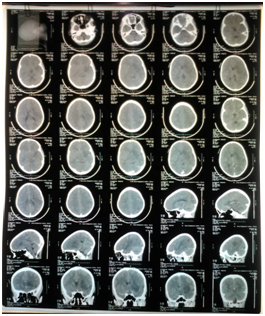

Patient was however noticed to have become aphasic, when he regained consciousness, and could not move his right upper and lower limbs. We managed as case of left hemispheric ischaemic stroke, the cranial CT (Figure 1) confirmed the diagnosis. The results of other investigations done are as follow: Packed cell volume was 31%, urine culture & sensitivity yielded no growth, electrolyte, urea and creatinine at admission and (the day after): Na 157.2 (146), Cl 107.6 (133.3), K 5.5 (4.77) and bicarbonate 17 (24), urea 22.6 (21.48), Creatinine 507.4 (160) and Malaria parasite (+++). In addition to controlling blood glucose with insulin, patient was also given IV Ceftriaxone for probable sepsis and IV Artesunate for malaria. Patient was co-managed by Paediatric endocrinologist, Paediatric neurologist and Physiotherapist, Nutritionist, and Paediatric nurses until patient was discharged home.

Figure 1 Cranial CT of index patient showing Left hemispheric ischaemic CVD.